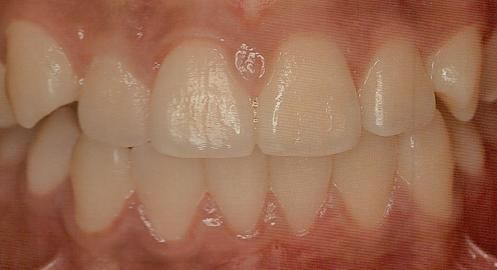

안녕하세요 목동안치과 안상우 원장입니다오늘은 뿌리만 남은치아를 살리는 방법에 대해서 알아볼꺼에요치아의 뿌리는 턱뼈에 고정이 되어 치아의 머리부위가 물리게 되서 음식을 저작하게 됩니다.그런데 치아가 외부충격이나 충치등으로 인해서 머리부위가 상실되게 되면 치아의 기능을 할수 없게 됩니다. 이런경우 치아가 없어진것 같아 보일수 있지만 실제적으로는 잇몸안에 뿌리가 남아 있는 경우가 많이 있어요.이런경 우에는 발치를 하지 않고 치아를 살릴 수 있는 방법이 있습니다.치과에서는 post라고 하는 치료 방법이 있습니다.post란 기둥을 의미하는 데요 치아에 기둥을 세우는 것이에요.부러진 치아에 기둥을 어떻게 세우냐고 하실수도 있습니다.치아 안 에는 신경이 있는 신경관이 있어요.파절이나 충치로 인해서 치아의 머리부위가 손상이 되었다면 신경관이 노출되게 됩니다.이렇게 노출된 신경관을 신경치료를 통해서 깨끗하게 청소를 하고 이후에 이 신경관에 기둥을 세우는 거에요.사진은 post 치료를 하는 과정입니다.신경관을 깨끗하게 정리 한 다음에 안쪽을 세척을 하게 됩니다.그 다음에 포스트와 치과용 시멘트를 이용해 뿌리부분이 머리 부분의 힘을 지탱할수 있도록 해줍니다.이후에 머리에 레진으로 수복을 하고 머리와 뿌리부분이 연결되도 하는 치료방법입니다치아에 들어가는 포스트 재료는 치아와 탄성이 거의 같은 fiber post를 사용하게 됩니다이렇게 되면 부러졌던 치아의 머리가 뿌리와 잘 결합이 되어 저작력을 지탱해 주게 됨으로써 치아의 기능을 할 수 있게 됩니다.결과적으로 없어진 것으로 생각했던 치아를 사용할 수 있게 된것이지요포스트 치료는 상실된 치아를 살려서 다시 사용할 수 있게 하는 좋은 치료방법입니다.하지만 포스트 치료를 하지 못하는 경우도 있습니다.치아가 파절이나 충치가 생겼을 때 손상된 부위가 잇몸뼈 아래로 진행이 되어 있게 되면 포스트 치료를 할 수 없어요.또한 포스트를 이용해서 치아를 살려도 교합력이 너무 강해서 제작한 기둥이 교합력을 정상적으로 버티지 못하는 경우도 있어요.보통 남성분들이 교합력이 강한 경우가 많은데요 이런 경우에도 포스트를 하기 힘들 수도 있어요하지만 치아를 발치하기 전에 포스트치료의 가능성에 대해서 알아보는 것은 치아를 보존할 수 있는 길이기도 합니다.치아는 한번 발치하면 이전 상태로 돌아가기 어렵기 때문이에요.